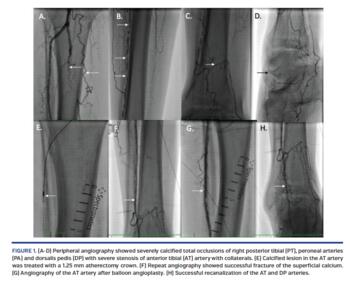

A 72-year-old man with critical limb ischemia of the right lower extremity was referred for revascularization. His peripheral angiography showed severely calcified total occlusions of the right posterior tibial artery, peroneal arteries, and dorsalis pedis, with severe stenosis of the anterior tibial artery with collaterals (Figures 1A-1D). In order to assess the vascular effects of rotational orbital atherectomy, we performed intravascular imaging with virtual histology intravascular optical coherence tomography (VH-IVOCT) (Figures 2A-2F).

We performed rotational orbital atherectomy of the calcified lesions in the anterior tibial artery using a 1.25 mm solid crown. Repeat angiography (Figure 1F) and VH-IVOCT (Figures 2B and 2E) showed successful fracture of the superficial calcium. Percutaneous transluminal angioplasty (PTA) was performed in the anterior tibial artery using a 3.5 mm balloon and in the dorsalis pedis artery using a 2 mm balloon. Final angiography showed successful recanalization of anterior tibial and dorsalis pedis arteries (Figures 1F and 1H). VH-IVOCT showed successful fracture of the calcium, leading to expansion of the lesions with a non-flow limiting dissection (Figures 2C and 2F). Blue color shows calcium in the vessel wall, green color, fibrous tissue and red color for lipid plaque.